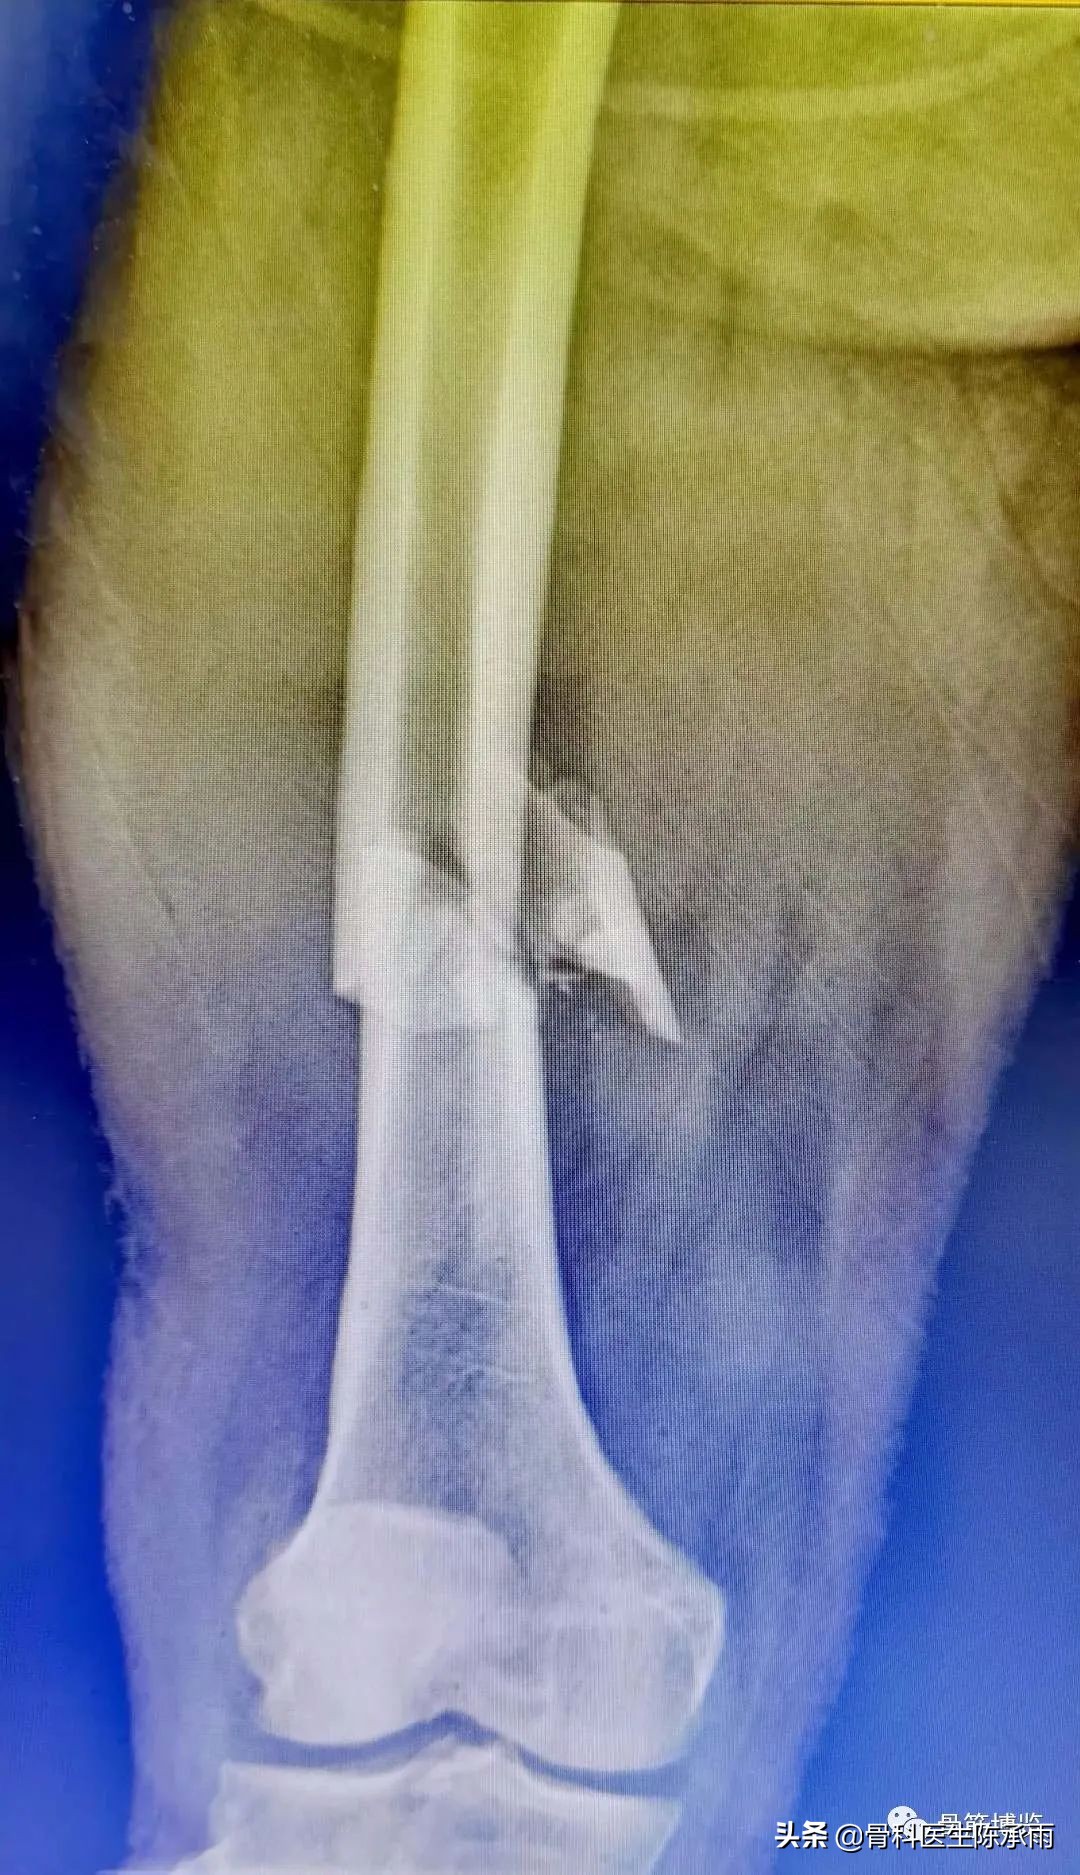

这2例患者皮肤条件差,全身多发骨折,小腿皮肤条件差,1例筋膜高压切开,1例整个小腿布满张力性水泡,胫骨骨折都在伤后30天才能手术。